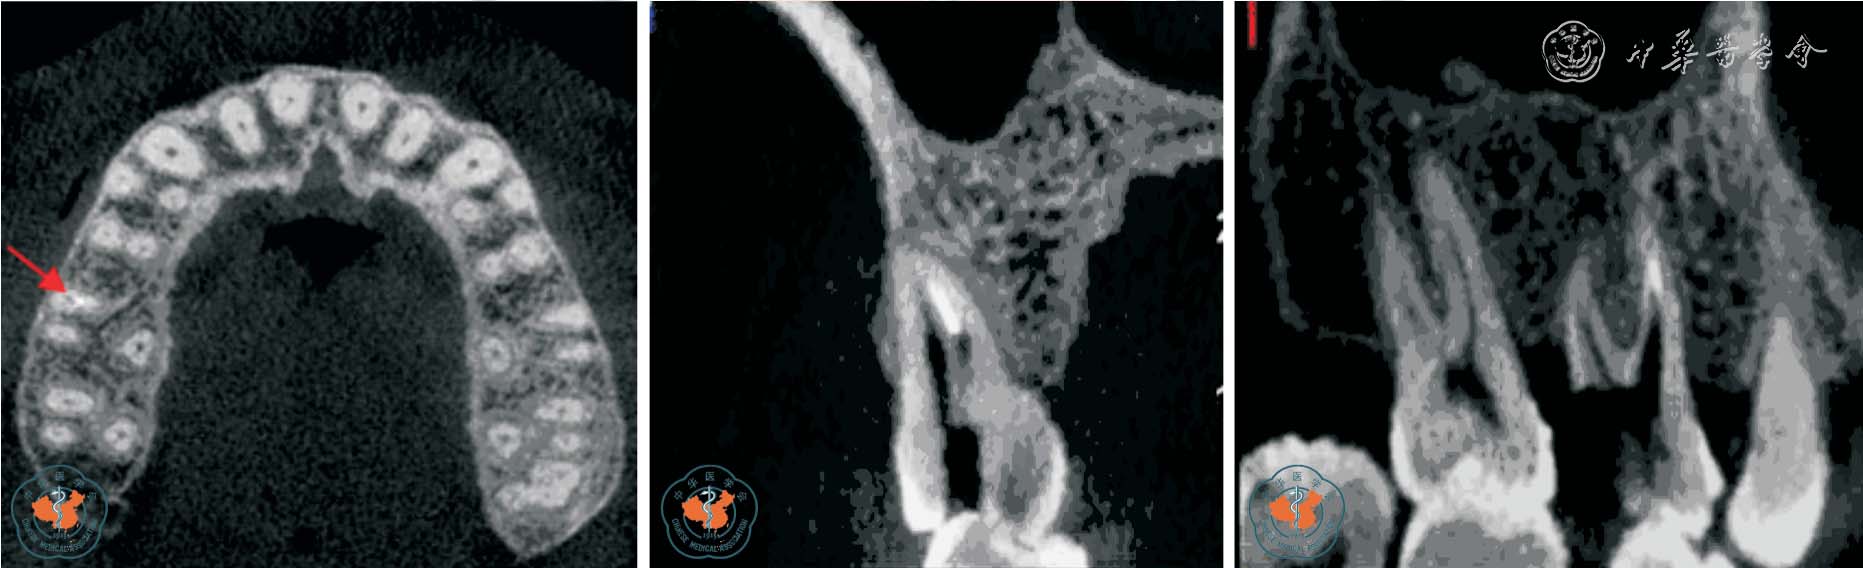

2. 观察牙根吸收情况:Tronstad12根据牙根吸收的起源部位将牙根吸收分为内吸收和外吸收,外吸收又根据不同临床表现分为炎症性外吸收、牙颈部外吸收和替代性外吸收。 早期牙根外吸收多无临床症状,X 线检查时才能发现。 由于根尖片只能显示相互重叠的二维影像,因此常不能清晰的显示吸收范围,难以准确评估牙根吸收的严重程度。 Estrela 等13报道指出根尖片识别牙根外吸收的假阴性率约为51.9%,假阳性率约为15.3%,尤其当病损位于颊侧或舌侧根面时,准确率更低。 而且,传统根尖片不能发现小于直径0.6 mm、深度0.3 mm的缺损。 CBCT 在很大程度上弥补了根尖片的缺点,其多层面重建(multiplannar reconstruction,MPR)技术可以显示病变的真实形态和部位,确定病变范围、破坏程度及周围牙槽骨的吸收状况,并可发现先前未发现的吸收缺损,有助于确定牙根吸收后的治疗规划,提高了患牙保存率(图3 ~4)。

图3 CBCT 轴位及MPR 重建显示上颌左、右第一磨牙牛牙症,其中左侧上颌第一磨牙根尖内吸收伴颊侧根折

图4 CBCT 轴位、VR、CPR 及MPR 重建冠、矢状位图像清晰显示根牙周病致牙根外吸收